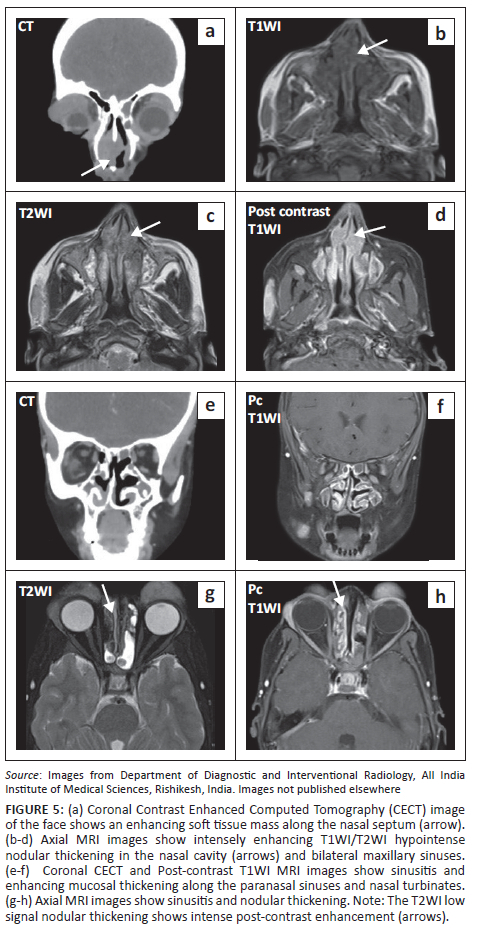

Pansinusitis was noted with homogeneously enhancing nodular thickening seen in the frontal, ethmoidal and maxillary sinuses bilaterally, along the nasal septum and involving the nasal turbinates. The corresponding CT scan showed no erosions of the sinus walls (Figure 5).

Nose and PNS involvement can present as nasal obstruction, epistaxis or olfactory abnormalities. Cross-sectional imaging can show enhancing polypoidal masses, thickening of the mucosa or opacification of the involved sinuses or nasal cavity. The lesions are usually hypointense on T2-weighted MRI. Bone erosion and adjacent soft tissue involvement are usually not seen. This in contrast to destructive diseases like granulomatosis with polyangiitis and lymphoproliferative disorders that form close differentials of the nose and PNS involvement.4 The PNS involvement in the presented case also had similar imaging features with enhancing T2WI hypointense polypoidal thickening and pansinusitis but no osseous erosion. Salivary gland lymphoid hyperplasia seen in the current case is another common presenting feature of RDD.1